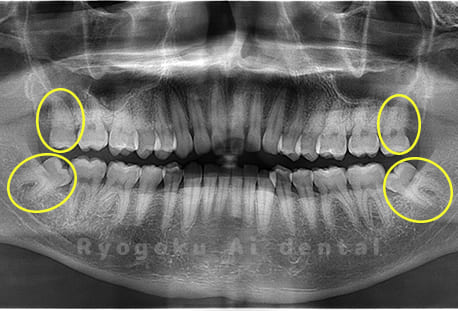

Case04

- 原因

- 上顎の親知らず、下顎の水平埋伏の親知らず

- 治療内容

- 上顎の親知らず、下顎の水平埋伏の親知らずを抜歯したケースです。

<リスク・副作用>

手術後は痛み、腫れ、痺れなどの副作用が生じる場合があります。